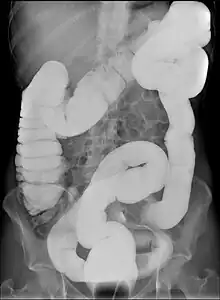

Dolichocolon is an abnormally long large intestine.[1] It should not be confused with an abnormally wide large intestine, which is called a megacolon.

Dolichocolon may predispose to abnormal rotation (see volvulus) and interposition between the diaphragm and the liver (see Chilaiditi syndrome). It is more commonly seen in the elderly, some psychiatric patients or in institutionalised individuals. It is not, however, a part of normal aging. The exact cause remains unknown. Dolichocolon is often an incidental finding on abdominal X-rays or colonoscopy. It is not by itself a disease and as such requires no treatment. The term is from ancient Greek dolichos, the long distance in running, and colon.